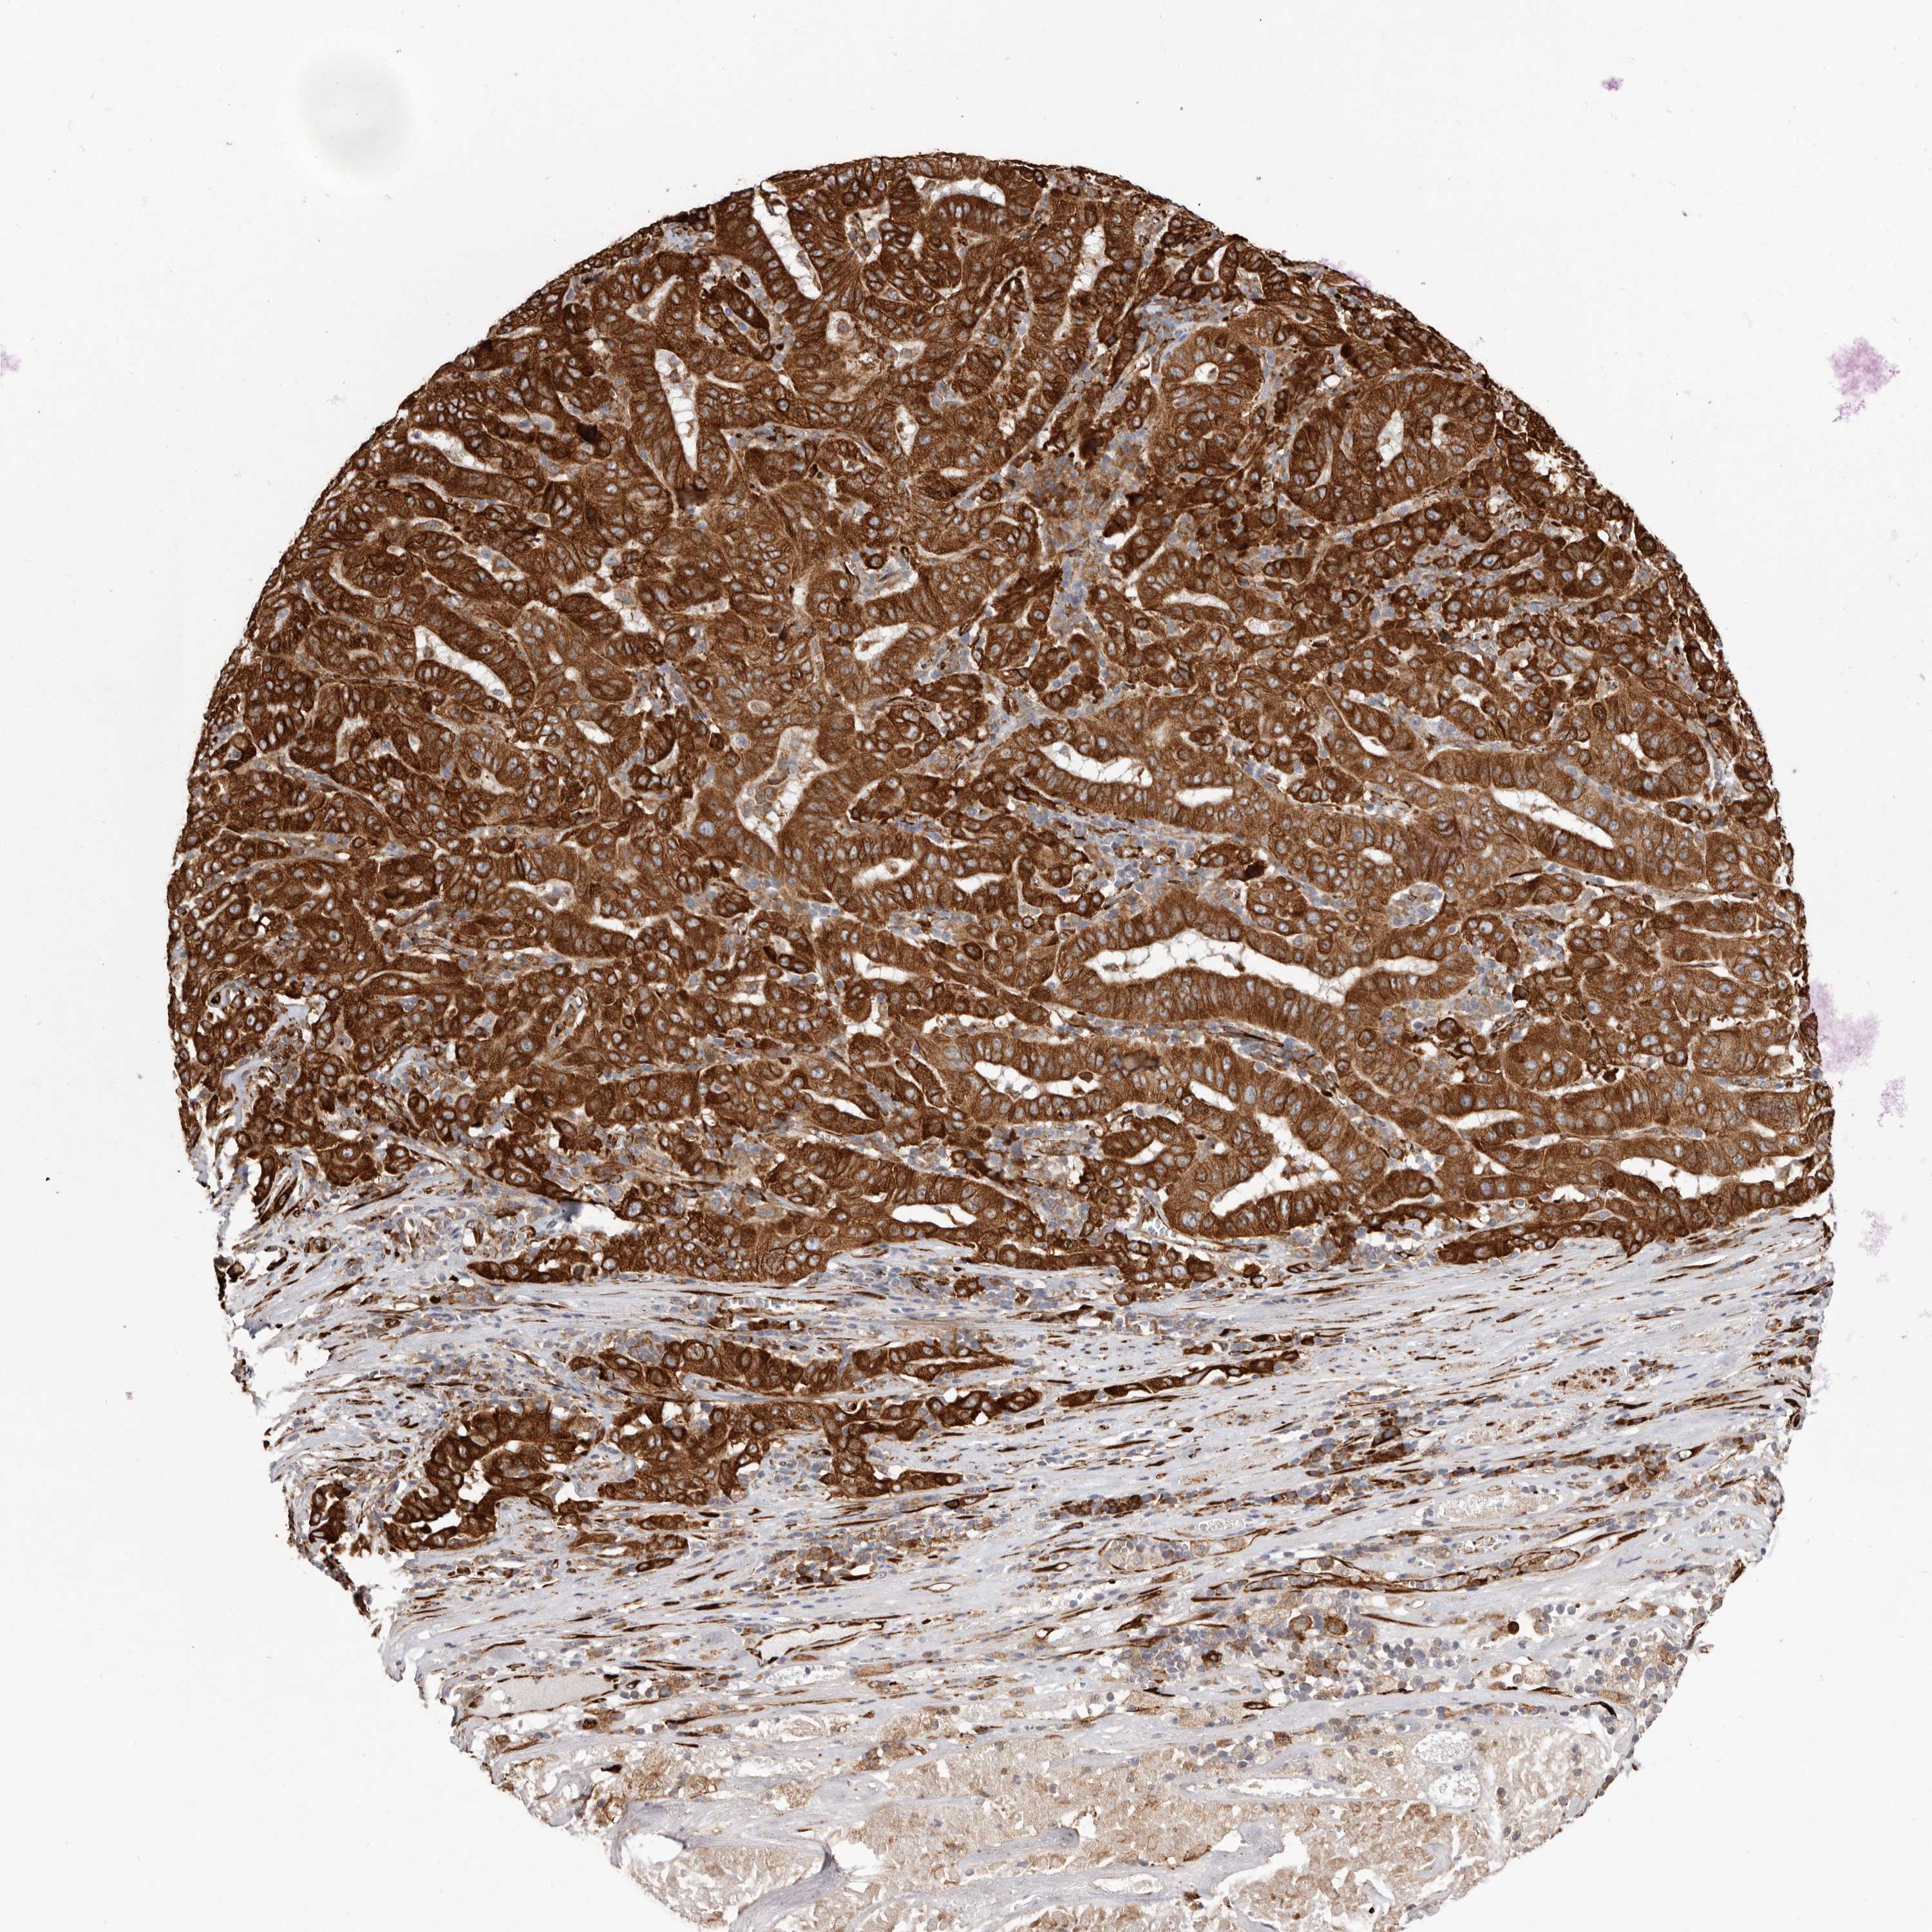

PANCREATIC CANCER - Protein expressioni

A mouse-over function shows sample information and annotation data. Click on an image to view it in a full screen mode. Samples can be filtered based on level of antibody staining by selecting one or several of the following categories: high, medium, low and not detected. The assay and annotation is described here.

Note that samples used for immunohistochemistry by the Human Protein Atlas do not correspond to samples in the TCGA dataset.

Antibody stainingi

Antibody staining in the annotated cell types in the current human tissue is reported as not detected, low, medium, or high, based on conventional immunohistochemistry profiling in selected tissues. This score is based on the combination of the staining intensity and fraction of stained cells.

Each image is clickable and will lead to virtual microscopy that enables deeper exploration of all samples and also displays staining intensity scores, fraction scores and subcellular localization as well as patient and tissue information for each sample.

Antibody HPA028177

Antibody HPA028180

Antibody HPA028182

Adenocarcinoma, NOS